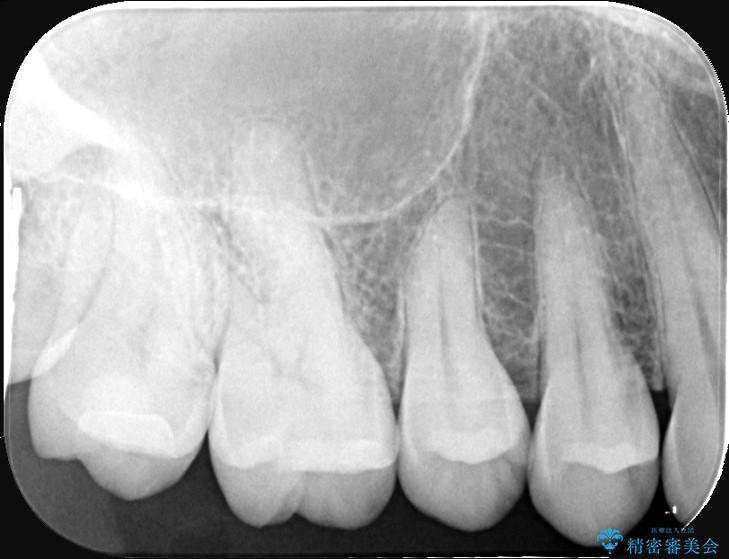

以前に詰めた白い詰め物の内部で、虫歯の再発が確認されました。

まずは古い詰め物と虫歯を丁寧に除去します。

除去後は、再発リスクを抑え長期的な安定を図るために、適合精度が高く劣化しにくいセラミックインレーによる修復を計画しました。